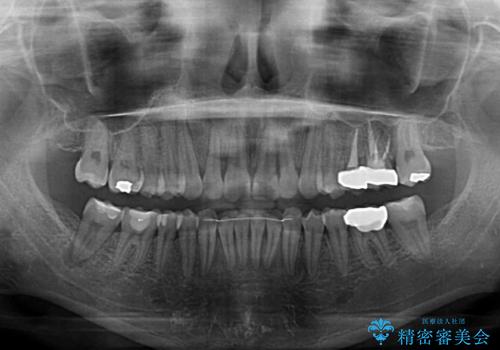

銀歯やムシ歯処置の必要な歯が奥歯にあり気になっていたので、矯正治療の途中でセラミッククラウンへ変更し、その後歯列を仕上げていくこととしました。

咬み合わせと目立っていた銀歯が改善され、患者様には大変満足していただきました。